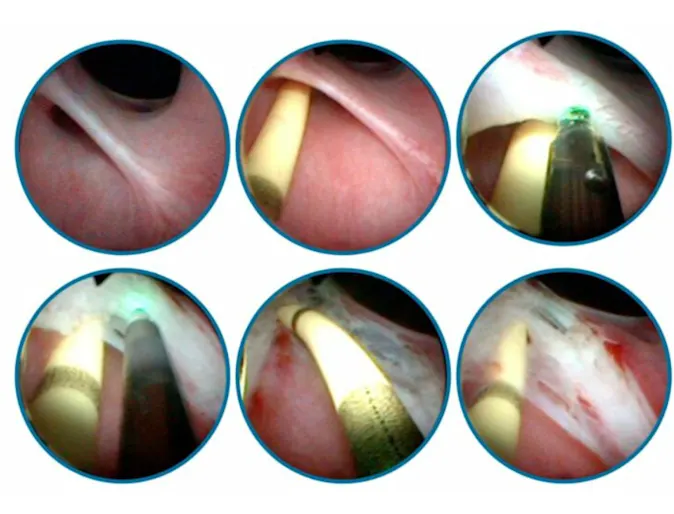

Stifle Arthroscopic TPLO in 6-year-old castrated Labrador Retriever

Surgery

One-month history of left hindlimb lameness (grade IV/V) with acute onset. The patient had a history of intermittent forelimb lameness that would resolve after 1-2 days of rest.